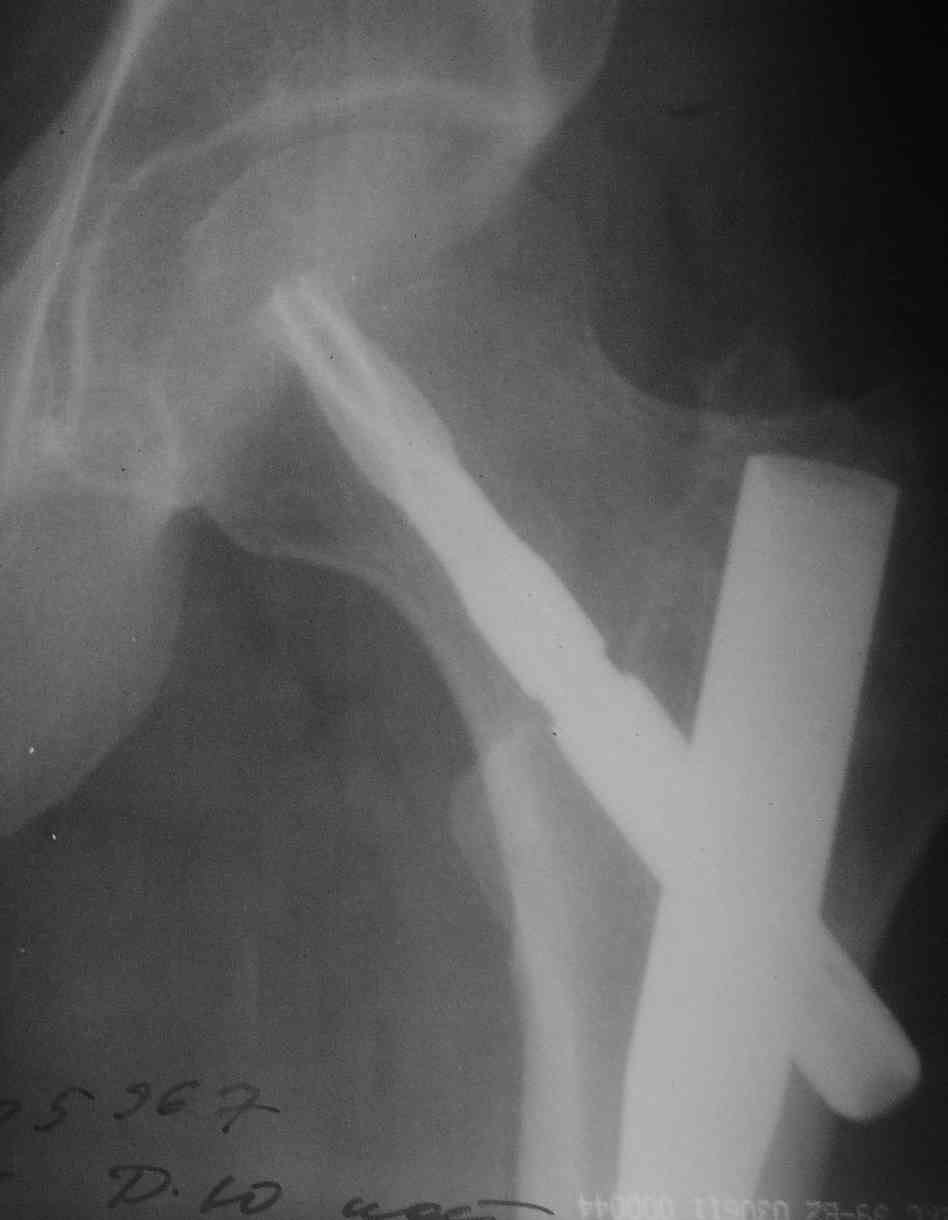

Молодой мыжик, была множественная травма. Снимок перед удалением вот.

Имя     : get_image1.jpg